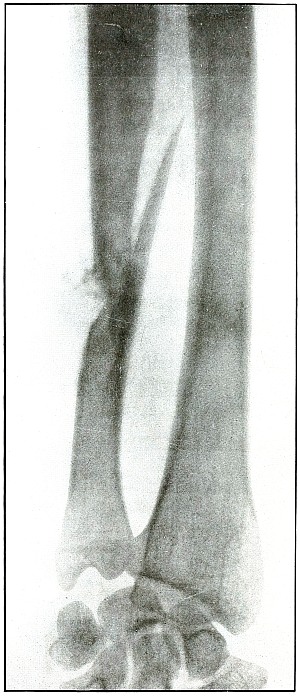

Plate 29.

[Pg 69]

Rifle—Plate 29.

UPPER EXTREMITY.

Gunshot Fracture of the Lower End

of the Radius.

The course of the bullet in long range was diagonally anteroposterior

through the ulnar side of the lower end of the bone, with the wound of

entrance on the anterior and the wound of exit on the posterior aspect

of the wrist. The wound of exit was slightly lacerated by several

small fragments driven off from the ulnar side of the radius. These

fragments were removed through an incision before the radiograph was made.

The emergency treatment of such cases is only antiseptic dressing and

splint immobilization.

When wound is aseptic or after it has closed, a secondary operation

for coaptation, with proper facilities available, might be indicated.

The results as to full restoration of joint function are not favorable.

[Pg 70]

Plate 30.

[Pg 71]

Rifle—Plate 30.

UPPER EXTREMITY.

Gunshot Fracture of the Lower End

of the Radius.

The course of the missile was diagonally transverse, striking the

radius in its lower third.

The projectile in this case is unknown, as it might have been either a

shrapnel ball or a deformed rifle bullet with a torn jacket, exposing

the lead core and marking its course with small particles of lead.

The fissures in the lower fragment and the finer fragmentation at the

seat of impact, indicate a great striking energy, that more often

resides in the high velocity of a rifle bullet than the low velocity

of a shrapnel ball. The wound is therefore classified with rifle wounds.

The treatment is conservative. The course in such cases, without

infection, is very favorable, and not unfavorable even with infection.

Results should be good.

[Pg 72]

Plate 31.

[Pg 73]

Rifle—Plate 31.

UPPER EXTREMITY.

Gunshot Fracture of the Lower End

of the Radius.

Wound of entrance, anterior aspect of wrist, over internal border of radius.

Wound of exit, posterior aspect of wrist between radius and ulna, with laceration.

The range was described as “close”—within a hundred yards—with

the bullet in high velocity. The energy of the projectile, imparted to

small fragments of cancellous tissue, drove them through the wound

of exit, and caused the laceration of the superficial tissues. The

wound was infected (swelling of soft parts clearly shown): resolution

followed extended treatment, with ankylosis of the wrist and radial

displacement of the carpus.

Emergency treatment in all such cases is antiseptic dressing

without exploration or manipulation of fragments, and with splint

immobilization.

Results are unfavorable as to function, depending upon extent of destruction of tendons.

[Pg 74]

Plate 32.